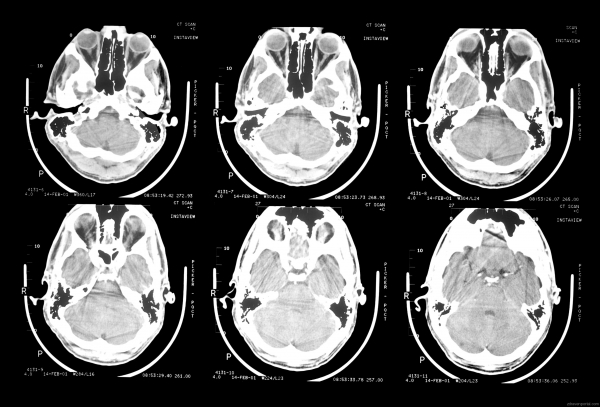

Китайски лекари са направили първото в историята успешно присаждане на човешка глава, съобщи италианският хирург Серджо Канаверо, който още през 2015 г. заяви, че се подготвя да извърши такава операция.

Първата трансплантация е направена върху труп. Следващата стъпка е операция на глава от донор с регистрирана мозъчна смърт, казва Канаверо, цитиран от британския „Телеграф“ и руската ТАСС.

Сложната операция е направена от лекари от медицинския университет в Харбин и е продължила 18 часа. През 2015 аз смятах, че за такава трансплантация ще са необходими 36 часа, но китайците са успели да съкратят наполовина времето, отбеляза Канаверо. В близките дни ще бъдат публикувани медицинските подробности за манипулацията.